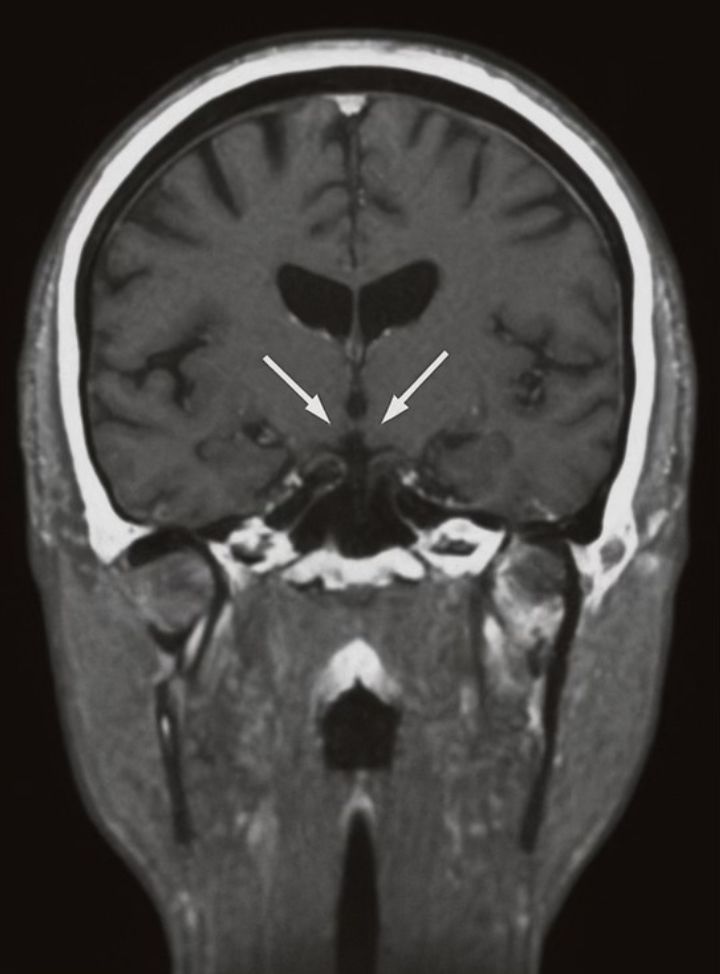

We report the case of a 26-year-old woman with severe, chronic AN (body mass index [BMI] 13.8 kg/m²) who was unresponsive to multiple therapeutic modalities. After a multidisciplinary evaluation, she underwent stereotactic implantation of bilateral electrodes targeting the subcallosal cingulate cortex.